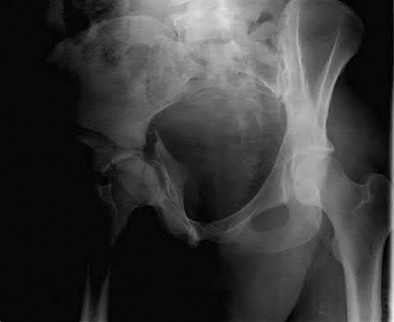

Which of the following images shows an injury pattern most consistent with a lateral compression type 3 pelvic ring injury?

Figure C is an axial CT scan of a lateral compression type 3 (LC3) pelvic ring injury.

Classically, LC3 injuries demonstrate an ipsilateral lateral compression and a contralateral APC (windswept pelvis) fracture pattern. The most common mechanism of injury in these cases is a rollover MVC or pedestrian vs. auto. LC1 injuries are characterized by an oblique or transverse ramus fracture and ipsilateral anterior sacral ala compression fracture, while LC2 injuries consist of a rami fracture and ipsilateral posterior ilium fracture dislocation (crescent fracture). While LC1 injuries can often initially be managed conservatively with protected weight-bearing and close observation, LC2 and LC3 pelvic ring injuries are almost universally operative.

Answer 1: This represents a lateral compression type 2 injury. Answer 2: This represents a lateral compression type 1 injury.

Answer 4: This represents an anterior posterior compression type 2 injury. Answer 5: This represents an anterior posterior compression type 3 injury.